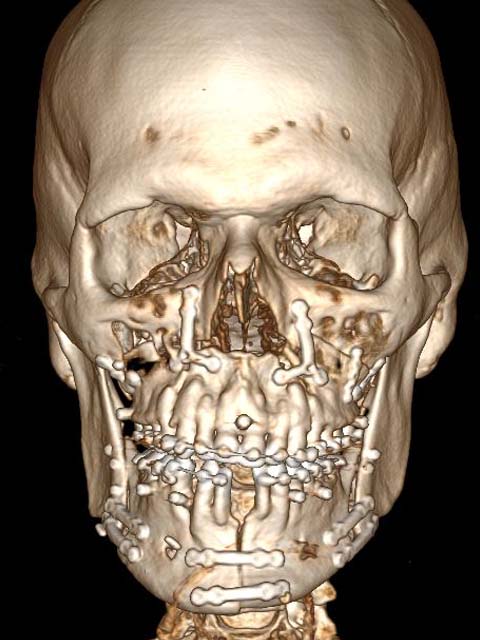

За 12 лет специалистами челюстно-лицевой и реконструктивной хирургии выполнено 7 586 операций разной степени сложности. На базе отделения впервые в России была проведена микрохирургическая реконструкция с резекцией нижней челюсти, пораженной опухолью, с одномоментной реконструкцией малоберцовым трансплантатом на сосудистой ножке с одномоментной дентальной имплантацией и протезированием зубов. В настоящее время данные хирургические вмешательства носят «рутинный характер» и проводятся в отделении еженедельно.

Бригадой хирургов отделения по руководством Давида Назаряна было принято решение о проведении сложного этапного лечения, включая реконструктивно-восстановительные операции, ортодонтическое лечение и протезирование зубного ряда. Не смотря на сложности послеоперационного периода и долгой реабилитации? Кирилл при поддержке команды челюстно-лицевых хирургов НМИЦО ФМБА России победил!

С момента удаления опухоли прошло более пять лет. Язык Кирилла не увеличился в размерах, рецидивов не наблюдается. В настоящее время Кирилл Баданов ведет полноценную жизнь молодого человека, обрел семью и с благодарностью обращается к врачам НМИЦО ФМБА России: «Мое внутреннее и внешнее состояние соответствует тому, что я всегда хотел».